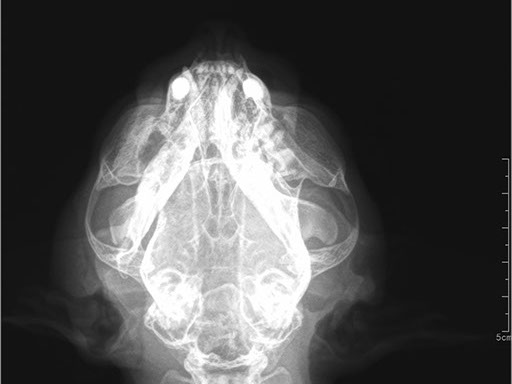

Коллиматорный прицел формирует пучок рентгеновского излучения на участок исследования. Проходя через ткани тела, излучение попадает на плоскопанельный цифровой детектор, который, в свою очередь, передает сигналы на компьютер.

В считанные секунды полученные данные обрабатываются компьютером посредством установленной на него программы визуализации, и сформированное клиническое изображение выводится на монитор лаборанта.